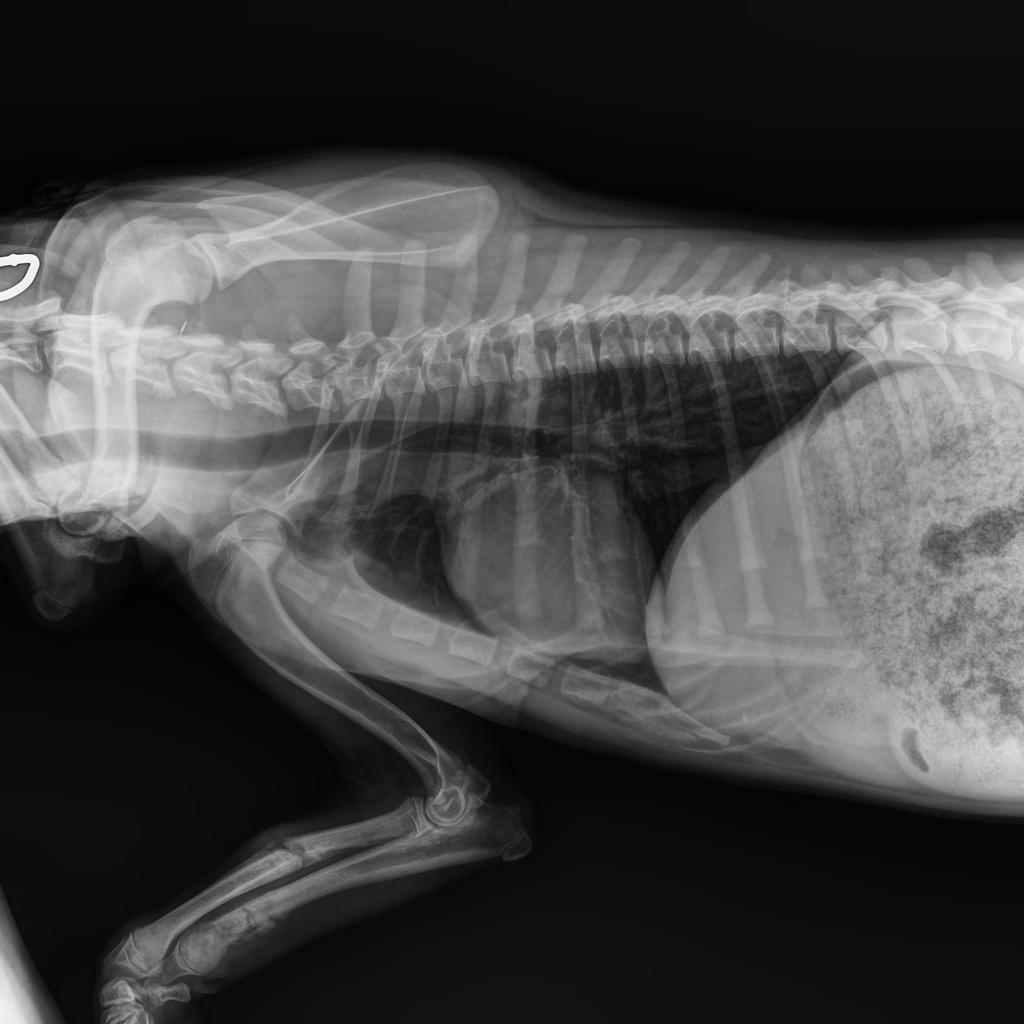

Der Klinikbericht zu der kleinen blinden Hündin ist da:

VETERINARY CLINIC Thessaloniki

„REPORT" Der Hund namens Nike wurde am 21/09/2022 mit neurologischen Symptomen vorgestellt: Ataxie, Desorientierung, Muskelzittern und unsicherer Gang. Nach der neurologischen Untersuchung wurde eine Erkrankung des Vorderhirns vermutet. Die Blutuntersuchung war innerhalb normaler Grenzen. Die Liquor-Analyse ergab keinen Hinweis auf eine Infektionskrankheit oder eine auf Steroide ansprechende Meningoenzephalitis. Es wird ein MRT des Gehirns und eine neurologische Untersuchung durch einen Facharzt für Neurologie empfohlen, um eine angeborene Hirnerkrankung zu bestätigen und die Prognose zu bestätigen. Die Untersuchungen von Nike sind beigefügt (s.Bilder)“

Diese Untersuchung (MRT) würden wir gern machen lassen, denn Nike hat ein Recht zu leben. Nur so können wir sie optimal fördern. Wir suchen also Paten, die mit uns für die kleine Kämpferin sorgen wollen. Bitte helft Nike!!!